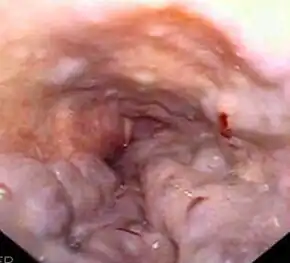

Both types of hepatorenal syndrome share three major components: altered liver function, abnormalities in circulation, and kidney failure. As these phenomena may not necessarily produce symptoms until late in their course, individuals with hepatorenal syndrome are typically diagnosed with the condition on the basis of altered laboratory tests. Most people who develop HRS have cirrhosis, and may have signs and symptoms of the same, which can include jaundice, altered mental status, evidence of decreased nutrition, and the presence of ascites.[6] Specifically, the production of ascites that is resistant to the use of diuretic medications is characteristic of type 2 HRS. Oliguria, which is a decrease in urine volume, may occur as a consequence of kidney failure; however, some individuals with HRS continue to produce a normal amount of urine.[7] As these signs and symptoms may not necessarily occur in HRS, they are not included in the major and minor criteria for making a diagnosis of this condition; instead HRS is diagnosed in an individual at risk for the condition on the basis of the results of laboratory tests, and the exclusion of other causes.[7]

Certain precipitants of HRS have been identified in vulnerable individuals with cirrhosis or fulminant liver failure. These include bacterial infection, acute alcoholic hepatitis, or bleeding in the upper gastrointestinal tract. Spontaneous bacterial peritonitis, which is the infection of ascites fluid, is the most common precipitant of HRS in cirrhotic individuals. HRS can sometimes be triggered by treatments for complications of liver disease: iatrogenic precipitants of HRS include the aggressive use of diuretic medications or the removal of large volumes of ascitic fluid by paracentesis from the abdominal cavity without compensating for fluid losses by intravenous replacement.[5]

Individuals with ascites that have become infected spontaneously (termed spontaneous bacterial peritonitis or SBP) are at an especially high risk for the development of HRS.[6] In individuals with SBP, one randomized controlled trial found that the administration of intravenous albumin on the day of admission and on the third day in hospital reduced both the rate of kidney insufficiency and the mortality rate.[26]